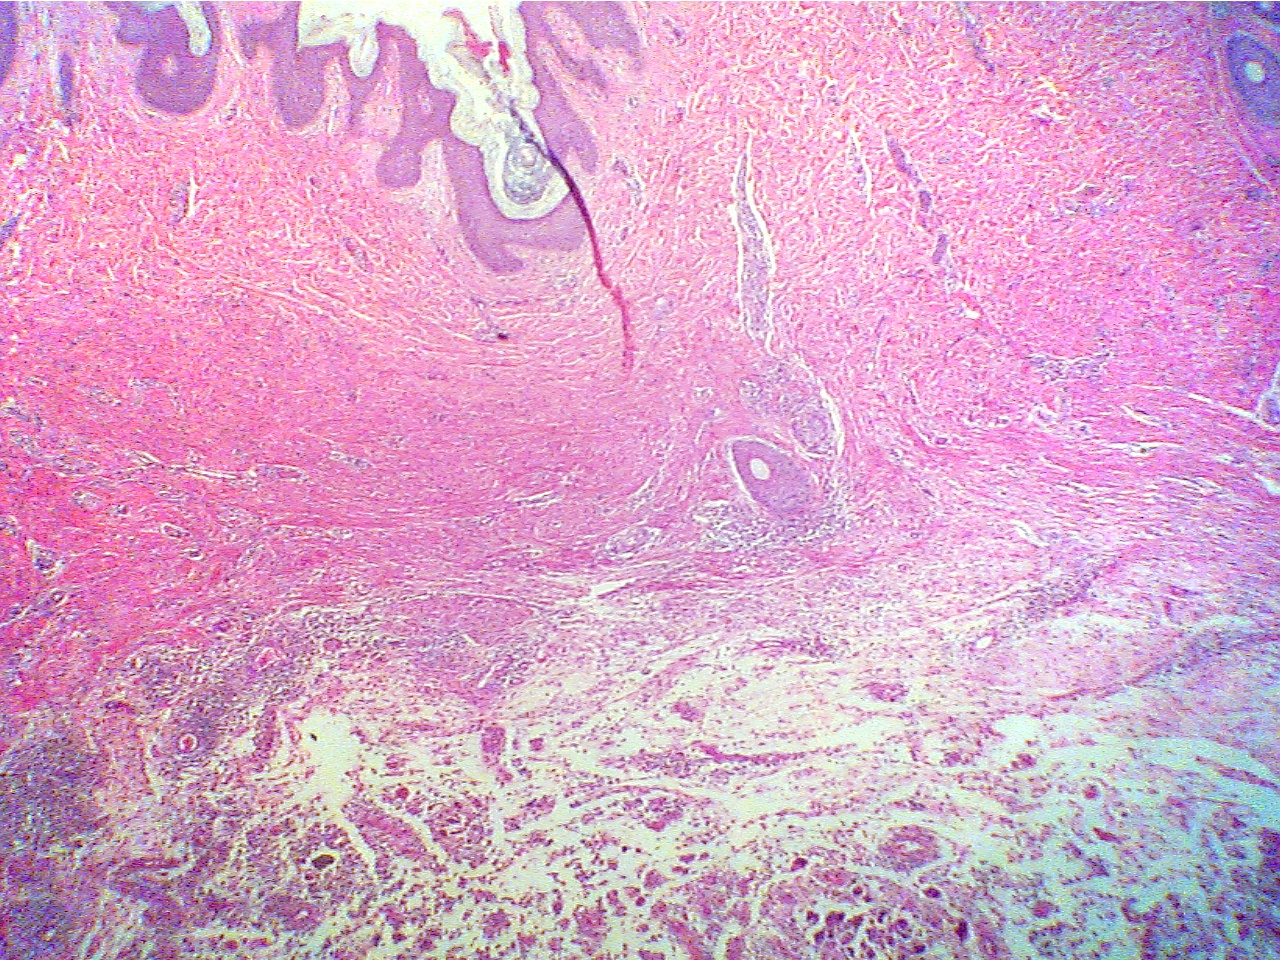

Abscess - Chronic Subcutaneous Abscess (PH 2335) (pp. 49-50)

Notice the spherical mass of unorganized cells and cell debris surrounded by

a capsule of fibrous connective tissue within the dermis of the skin. Compare

its appearance with the normal dermis by moving the slide back and forth.

Subcutaneous abscess (40X1.0)

Epidermis (thin dark layer at top), dermis

(thick

Edge of dermis (fibers at top), pus (scattered cells

red layer), edge of abscess (scattered dark

cells

and debris in clear liquid at bottom)

and debris at bottom)